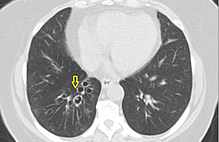

Cureus | Red Dot Basal Cell Carcinoma: Report of Cases and Review of This Unique Presentation of ...

Cureus | Red Dot Basal Cell Carcinoma: Report of Cases and Review of This Unique Presentation of ... from assets.cureus.com